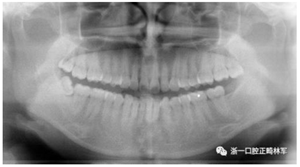

X線片檢查分析

初診全景片:牙齒數(shù)目形態(tài)未見(jiàn)異常,牙根未見(jiàn)異常。48近中阻生。